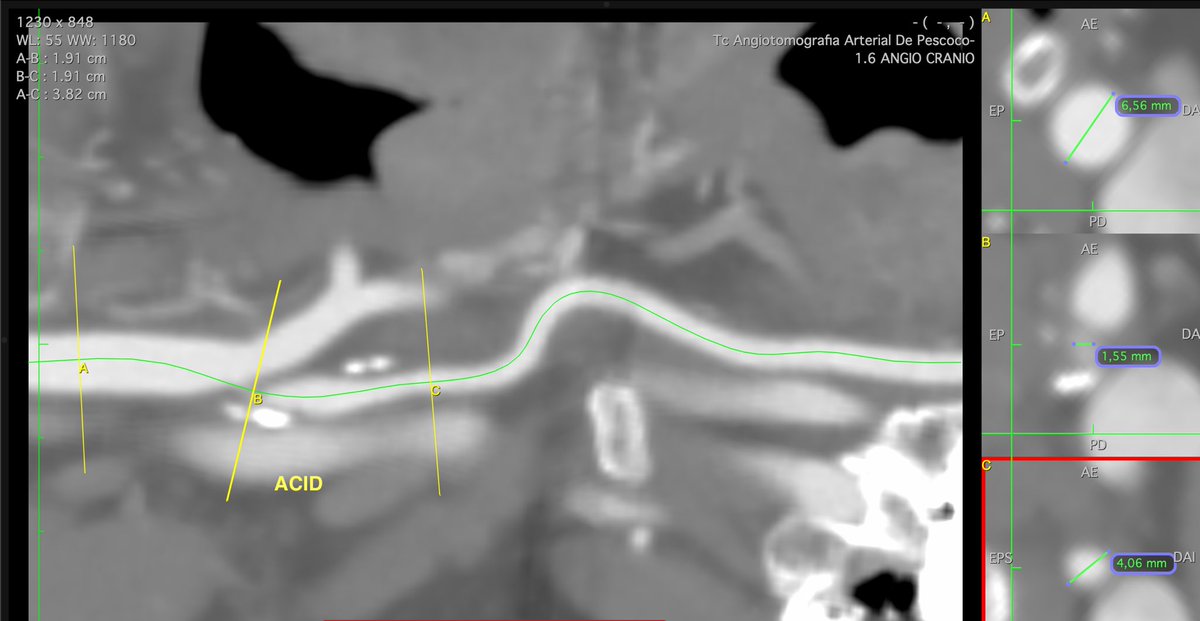

FEVAR with Diameter Reducing Ties plus 4 preloaded through-and-through wires for a small lumen case. Access from above. #AortaEd @gracemulatti @paulomenezesf @cfbechara @fonseca_alan5 @AndrePoci